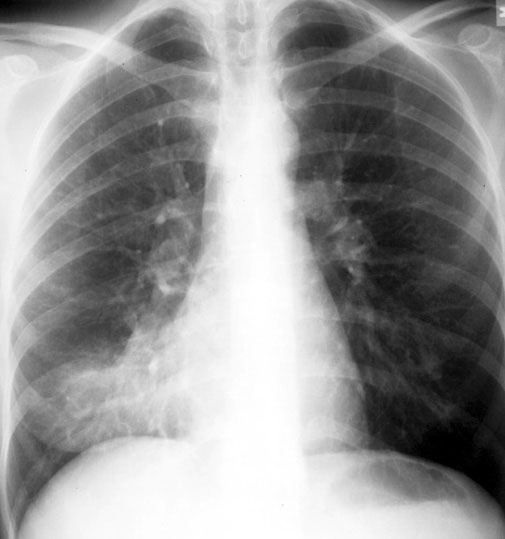

Pneumonia is a severe health condition in which bacteria, fungi, or viruses cause an infection in one or both lungs. When infected, the air sacs fill with pus and other liquids. Some common symptoms include a productive cough, chills, fever, and difficulty breathing. Treating this condition immediately before it worsens and leads to other concerns is essential. Let’s look at some of the risk factors and classification of the disease.

Pneumonia has many causes, and all of them are classified into different categories. According to experts, more than 30 different causes can develop this condition. Some types of pneumonia are:

While other factors like fungi can also cause the condition, such cases are less common. Note that when one or more parts of the lungs are affected, it is called lobar pneumonia; when the infection is in patches throughout both lungs, it is called bronchial pneumonia.